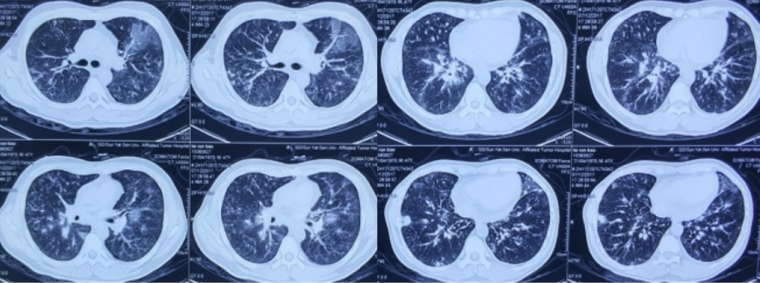

2017年12月12日患者仍有明显气促,氧合无改善,氧合指数120~130 mmHg,复查胸部CT双肺病变较12月6日明显进展(图3)。